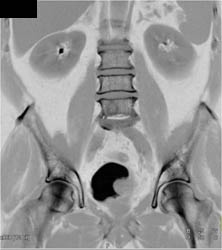

Bladder Cancer